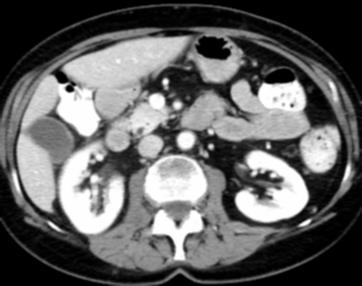

Due to the constraints of the imaging device and high cost in operation time, computer tomography (CT) scans are usually acquired with low intra-slice resolution. Improving the intra-slice resolution is beneficial to the disease diagnosis for both human experts and computer-aided systems. To this end, this paper builds a novel medical slice synthesis to increase the between-slice resolution. Considering that the ground-truth intermediate medical slices are always absent in clinical practice, we introduce the incremental cross-view mutual distillation strategy to accomplish this task in the self-supervised learning manner. Specifically, we model this problem from three different views: slice-wise interpolation from axial view and pixel-wise interpolation from coronal and sagittal views. Under this circumstance, the models learned from different views can distill valuable knowledge to guide the learning processes of each other. We can repeat this process to make the models synthesize intermediate slice data with increasing inter-slice resolution. To demonstrate the effectiveness of the proposed approach, we conduct comprehensive experiments on a large-scale CT dataset. Quantitative and qualitative comparison results show that our method outperforms state-of-the-art algorithms by clear margins.